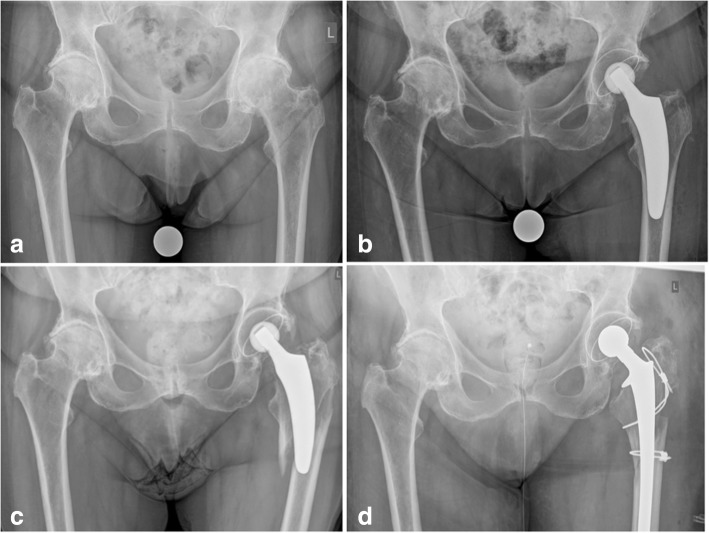

In all patients, a cementless calcar-guided short stem (optimys, Mathys Ltd. Bettlach, Switzerland), which is available in 12 different sizes with a 12/14 mm taper and 2 different offset versions, was implanted (Fig. 1). A rough titanium plasma sprayed coating, and a calcium phosphate coating are provided to ensure safe metaphyseal anchorage in the femoral bone. The stem is aligned along the proximal medial cortex and the calcar femorale. Anchoring is based on the fit-and-fill principle and can be done as classic 3-point anchoring [7].

Fig. 1.

The optimys short stem (Mathys Ltd., Bettlach, Switzerland)

Postoperative periprosthetic femoral fractures during follow-up were observed in 0.4% in the young group and 3.6% in the elderly group respectively, the difference being statistically significant (p = 0.02). Three of these periprosthetic fractures led to stem revision and the other 3 were successfully treated conservatively with no weight bearing using crutches (Figs. 3 and 4). Whereas in Dorr type A femurs no postoperative periprosthetic fracture was observed at all, in type B femurs a total of 4 fractures occurred and in type C femurs a total of 2 fractures occurred respectively. Thus, the incidence of postoperative periprosthetic fractures in Dorr type B and Dorr type C femurs was 2.1 and 22.2%, respectively (p = 0.0001) (Table 5).

Fig. 3.

Example of postoperative periprosthetic fracture Vancouver type B3 due to accidental fall of an elderly female patient followed by stem revision (a: preoperative; b: postoperative; c: periprosthetic fracture; d: after stem revision)